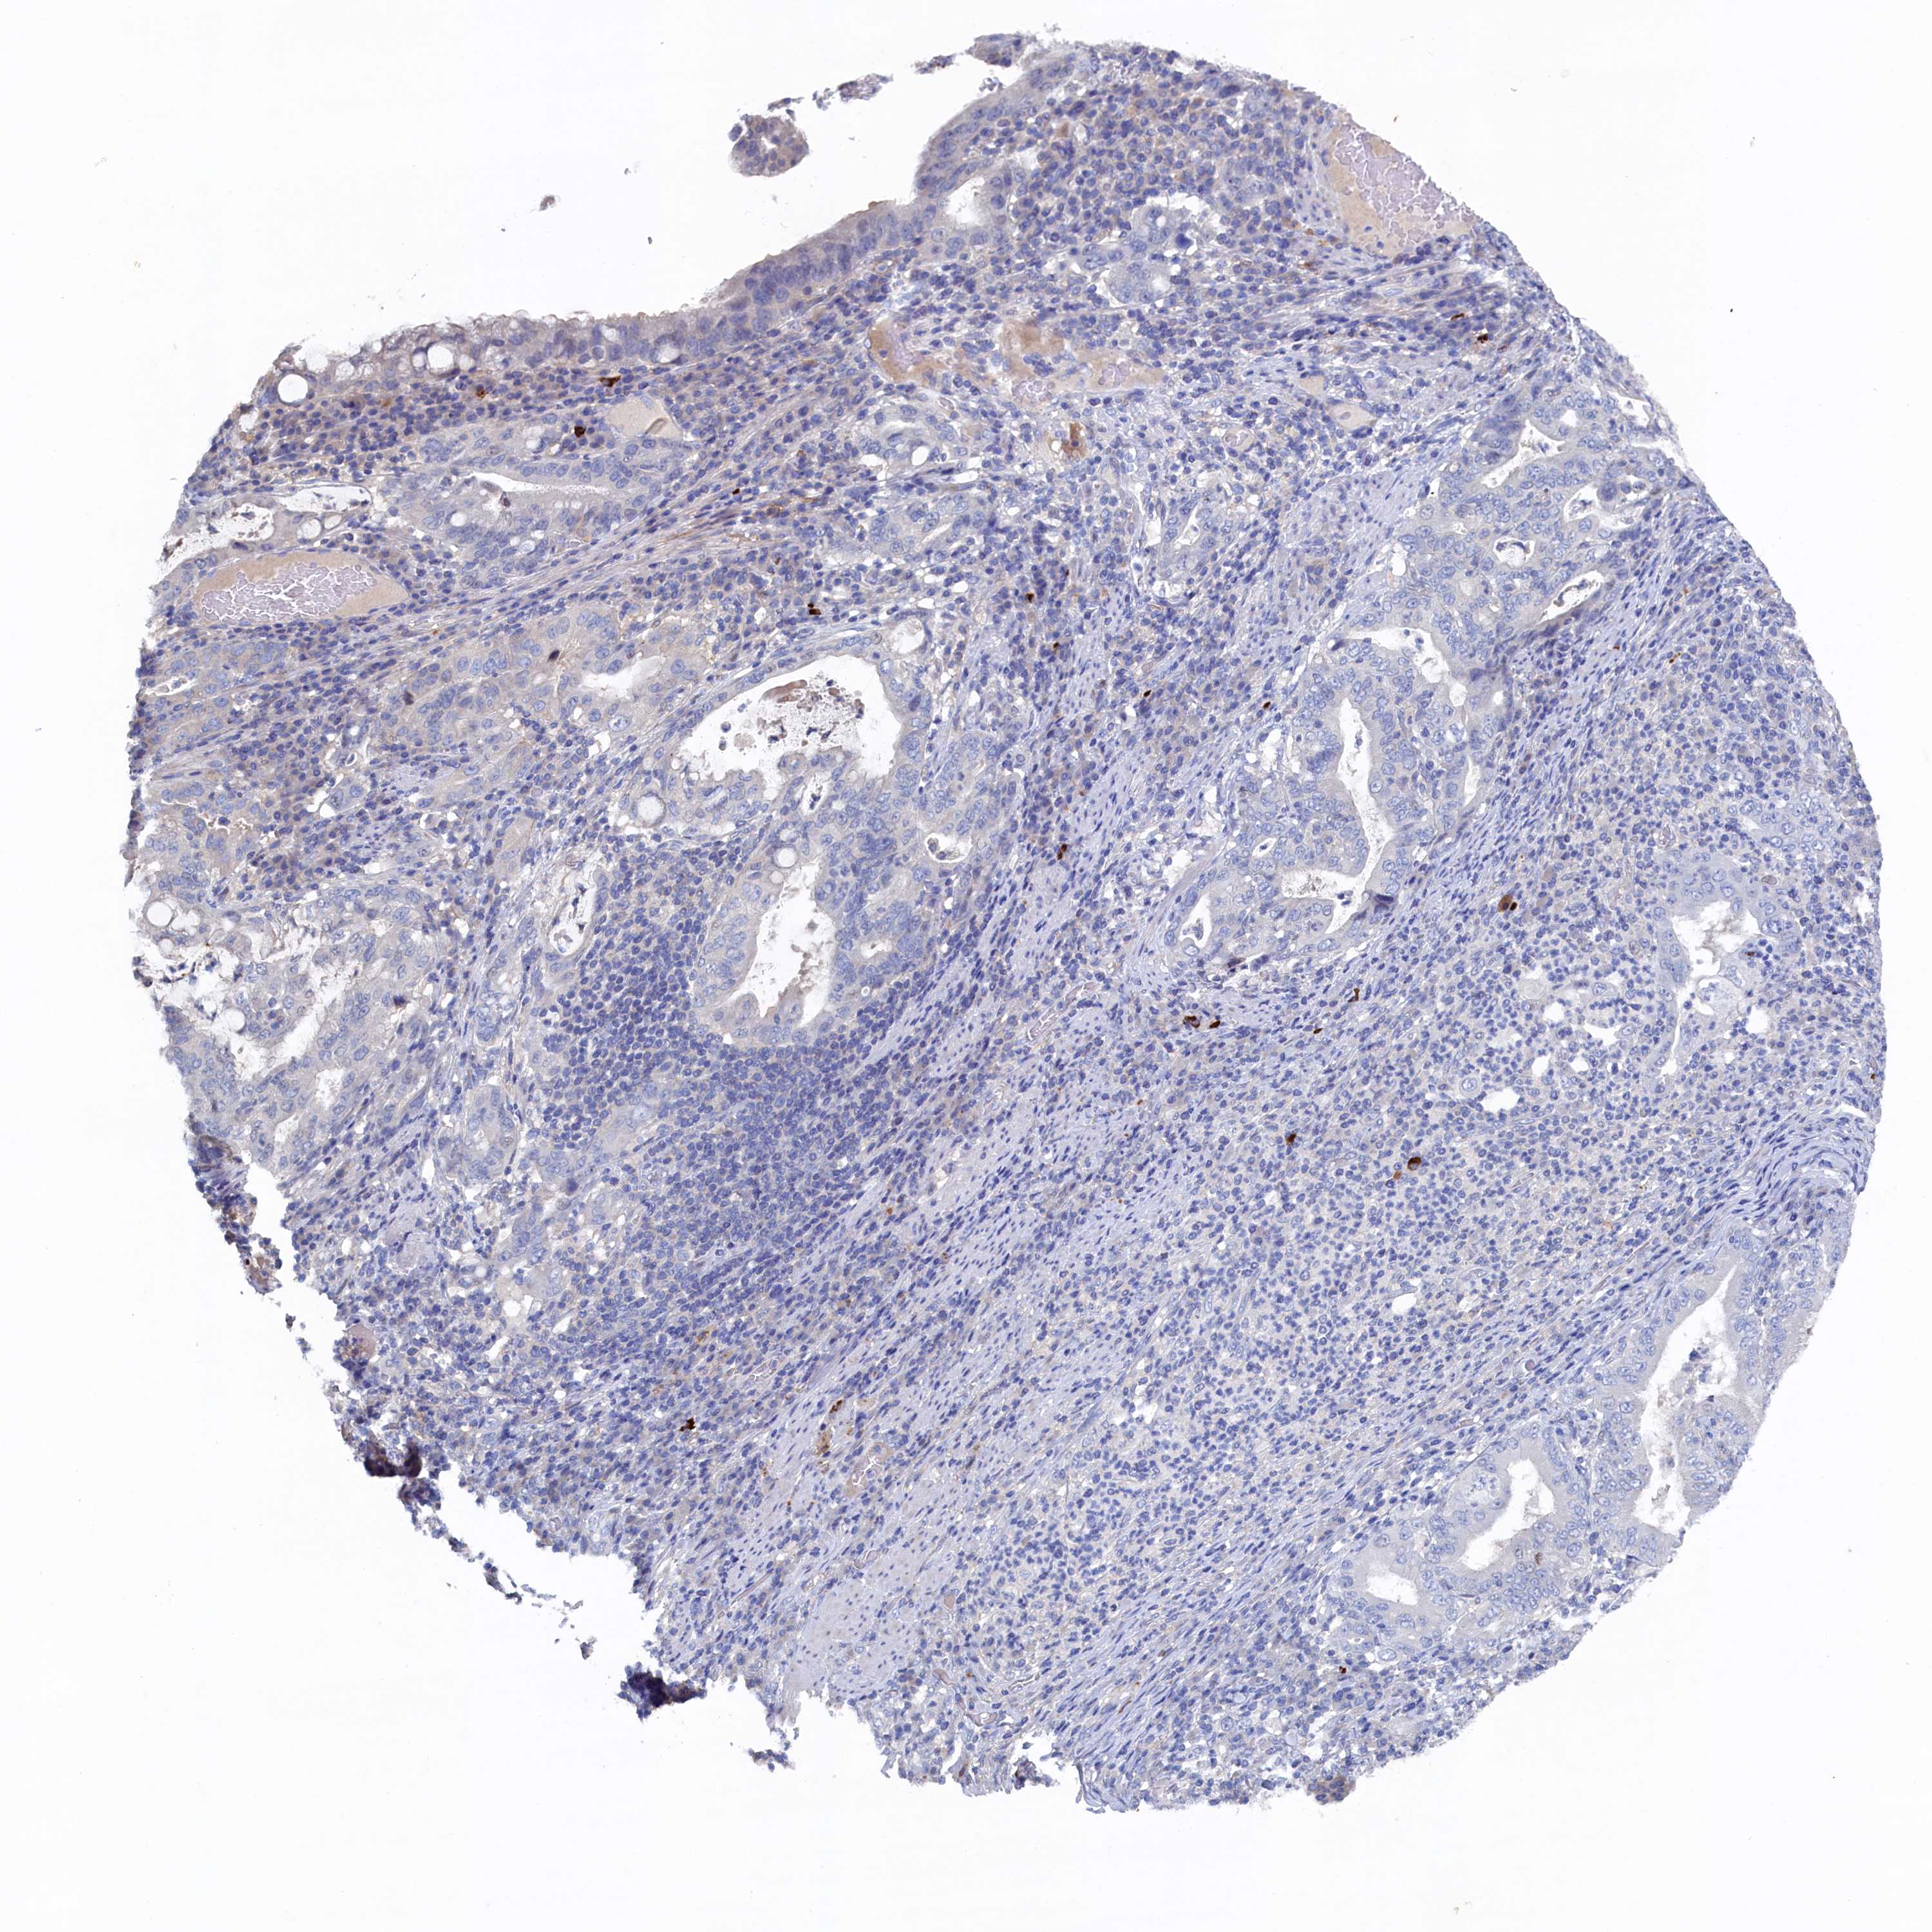

STOMACH CANCER - Protein expressioni

A mouse-over function shows sample information and annotation data. Click on an image to view it in a full screen mode. Samples can be filtered based on level of antibody staining by selecting one or several of the following categories: high, medium, low and not detected. The assay and annotation is described here.

Note that samples used for immunohistochemistry by the Human Protein Atlas do not correspond to samples in the TCGA dataset.

Antibody stainingi

Antibody staining in the annotated cell types in the current human tissue is reported as not detected, low, medium, or high, based on conventional immunohistochemistry profiling in selected tissues. This score is based on the combination of the staining intensity and fraction of stained cells.

Each image is clickable and will lead to virtual microscopy that enables deeper exploration of all samples and also displays staining intensity scores, fraction scores and subcellular localization as well as patient and tissue information for each sample.

Antibody HPA039908

Antibody HPA040774

Staining

High

Medium

Low

Not detected

Intensity

Strong

Moderate

Weak

Negative

Quantity

>75%

75%-25%

<25%

None

Location

Nuclear

Cytoplasmic/membranous

Cytoplasmic/membranous,nuclear

Adenocarcinoma, NOS

Adenocarcinoma, High grade